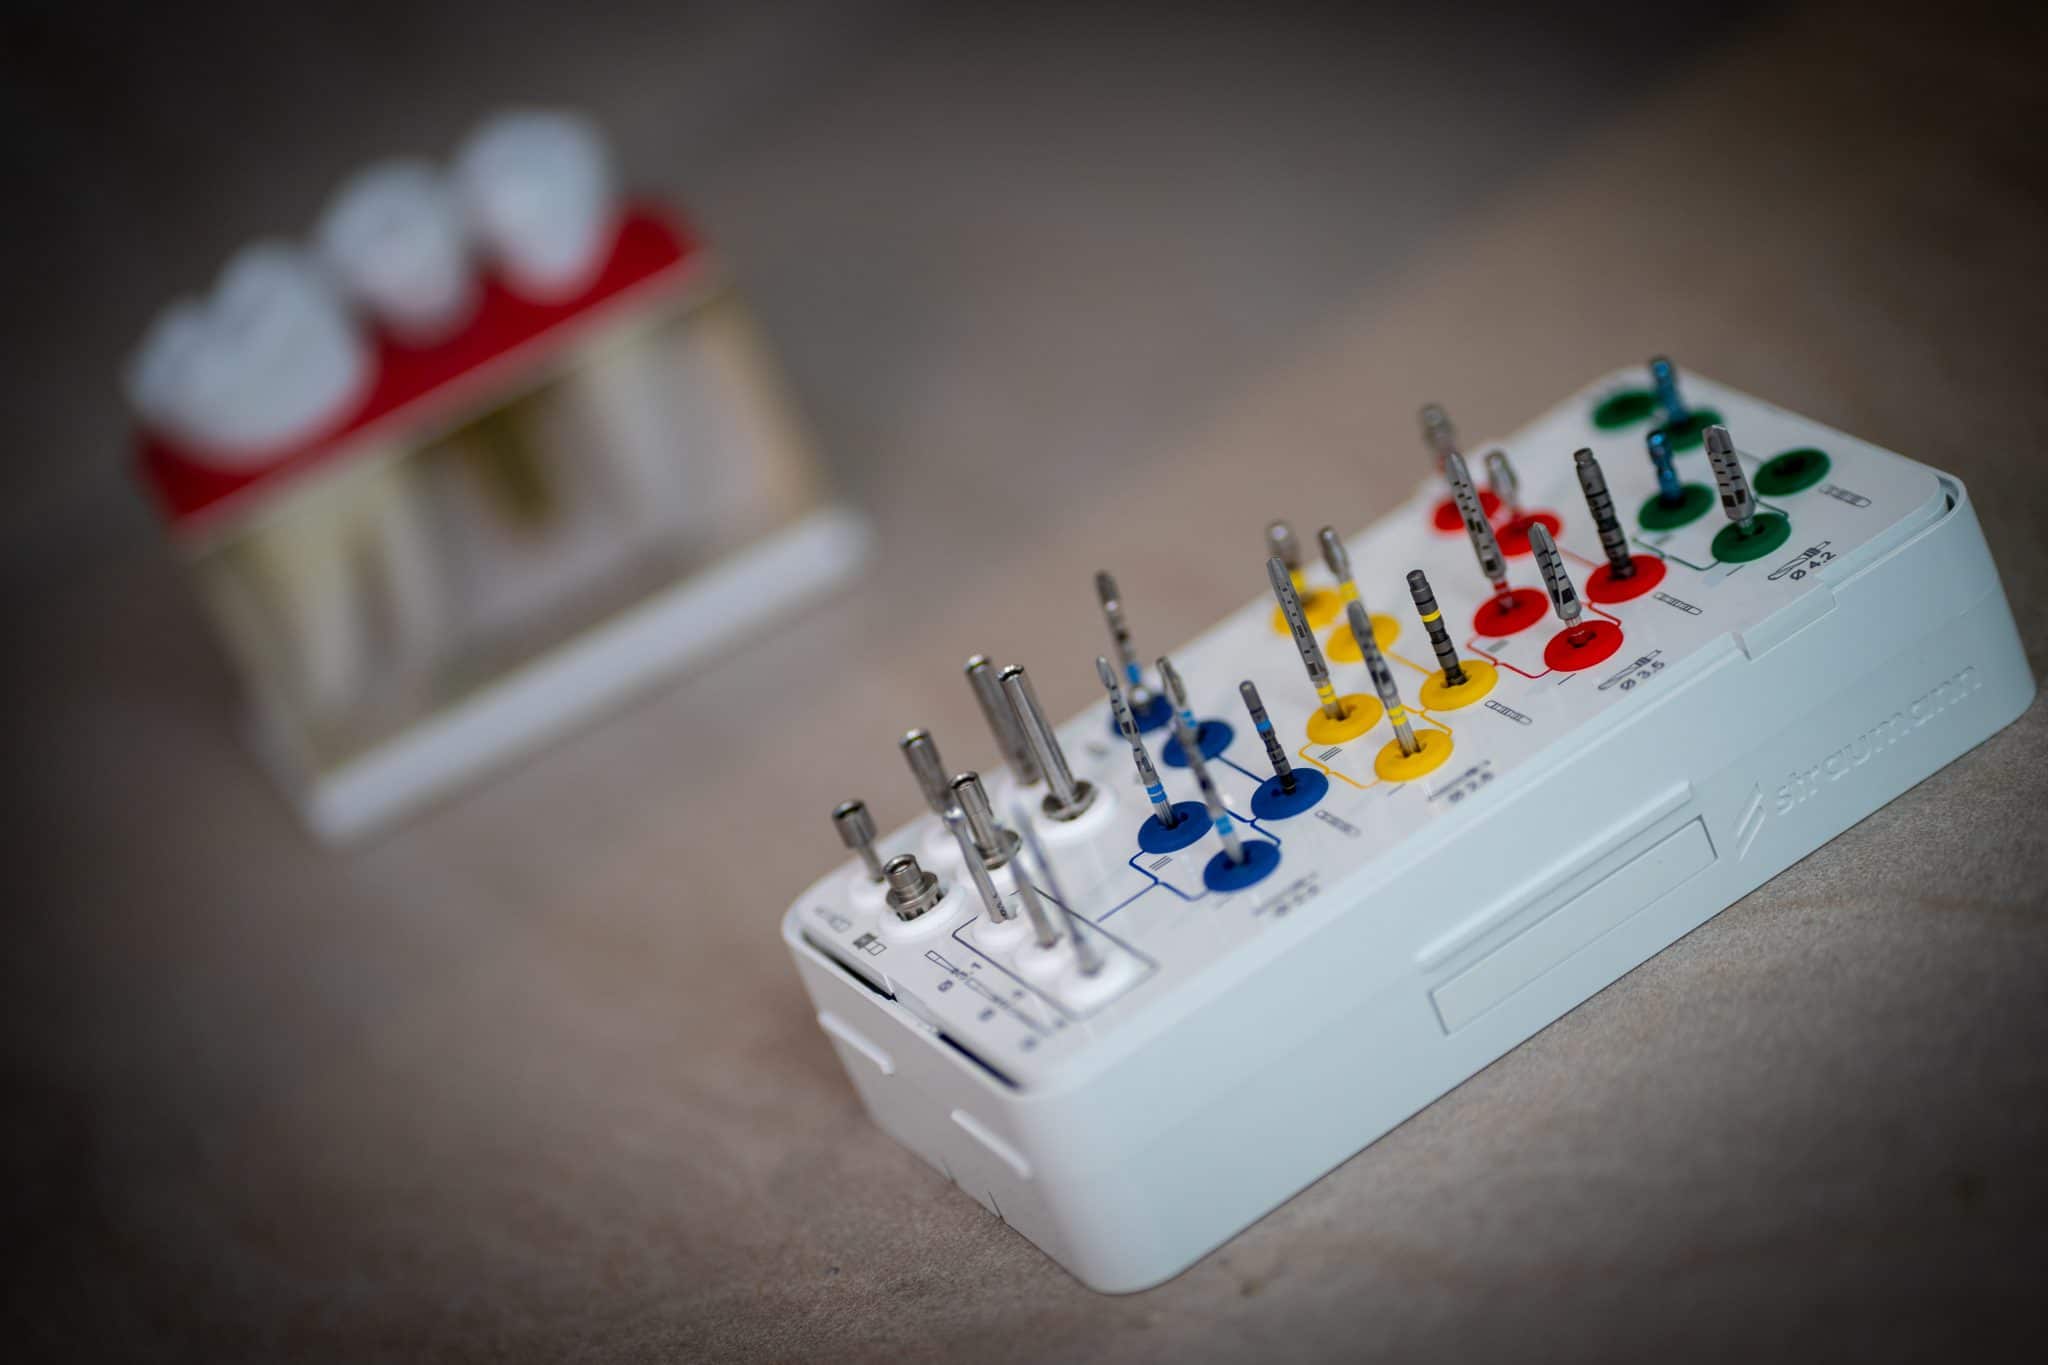

Az implantátum ágyat fúrási sorozattal készítjük elő, ezt követően betekerjük a műgyökeret. Egy egyszerűbb esetben akár 15 perc alatt elvégezhető a beavatkozás, míg komplikáltabb esetekben ez akár 1-2 óra is lehet.

Az implantátumra készíthető felépítmények, fejek típusai

Az implantátum felépítmény vagy közti elem/fej az a speciális rész, melyet az implantátumba csavarozunk és az implantátumot köti össze a fogpótlással. Ennek kialakításának, milyenségének nagy a jelentősége, hiszen az ínyen keresztül biztosítja az implantátum és a pótlás közötti összeköttetést, valamint a fogpótlás alapját. Többféle anyagból készülhet, leggyakrabban titánból vagy cirkóniumból. A cirkónium nagy előnye, hogy fehér színe révén rendkívül esztétikus, illetve az íny is jobban megtapad rajta.

Az implantátumokra készült kivehető fogsorokat speciális rögzítő elemekkel, pl lokátorokkal, merevítő rudakkal, stégekkel tartjuk helyben.

Az implantátumokra készülő rögzített pótlások (koronák, hidak) esetén az implantátumhoz való rögzítés történhet csavarozott illetve cementezett felépítménnyel.

A cementezett felépítmény készítése során az implantátumba csavarjuk a fogtechnikus által becsiszolt implantátumfejet, majd erre egy speciális ragasztócementtel ráragasztjuk az elkészült fogpótlást. Nagy hátránya, hogy végleges ragasztócement használata esetén a fogpótlás nem távolítható el (csak a korona átvágásával, vagyis végleges roncsolásával). Amennyiben a későbbiekben a koronával vagy az implantátummal, az implantátum körüli szövetekkel probléma adódik, az egyetlen megoldás a pótlás eltávolítása majd újra készítése. Másik hátránya, hogy a rögzítéshez használt ragasztócement a korona/híd felhelyezése során kifolyik az íny alá, és sok esetben a legnagyobb igyekezet mellett sem távolítható el tökéletesen, ezzel az implantátum körüli szövetek irritációját, gyulladását okozva. A cementezett implantátumos fogpótlások előnye a csavarozottakkal szemben, hogy jóval olcsóbbak, illetve extrém nagy szögeltérés esetén is alkalmazhatók.

A csavarozható felépítmények legnagyobb előnye eltávolíthatóságuk. A csavarnyílást rögzítéskor a csavar megfelelő nyomatékra húzása után tömőanyaggal zárjuk. Ez a tömőanyag a későbbiekben bármikor eltávolítható, a csavar vagy csavarok meglazíthatóak, ezáltal a rögzítés az implantátum és a pótlás közt megszűnik, a pótlás eltávolítható (javítás, ellenőrzés, tisztítás céljából). Természetesen ebben az esetben nem kell az esetlegesen íny alatt maradt ragasztócement miatt aggódnunk.

Hátránya a csavarozott felépítményeknek, hogy jóval drágábbak, mint a cementezett változat.

Rengeteg féle implantátum, implantációs rendszer létezik, mi a rendelőnkben kétféle rendszert (két gyártótól) használunk, de azokon belül is több féle implantátum (formájú, felszínű stb.) létezik, attól függően, hogy milyen helyzetben melyik a legmegfelelőbb.

Alapvetően egy egészséges páciens esetén, aki megfelelő csont és lágyszövetekkel (vastag, feszes ínnyel) rendelkezik szinte mindegy. Általánosságban azonban elmondható, hogy amennyiben csontpótlásra van szükség, vékonyabb implantátumokat szeretnénk behelyezni vagy van valamilyen rizikó faktor (pl. cukorbetegség, fogágybetegségre való hajlam stb.) érdemes a jobb/drágább implantátumot választani. A rendelőnkben használt Straumann implantátum speciális titán-cirkónium ötvözetből (Roxolid®) készül, amely sokkal ellenállóbb, így vékonyabb átmérőben is biztos megoldást jelent.

Továbbá létezik egy speciális hidrofil felszínnel (SLActive®) rendelkező Straumann implantátum, amely sokkal gyorsabban becsontosodik (akár 6 hét után elkészíthető rá a végleges pótlás), valamint sokkal jobb a csontosodási hajlama ezért komplikáltabb szituációkban javasoljuk (rossz minőségű csont, csontpótlás, cukorbetegség stb).

Ez nem csak magát a titán csavart foglalja magába, amit a csontba helyez a szájsebész, hanem számos egyéb kiegészítő elemet is. Így a felépítményt (az implantátumot a koronával összekötő elem), a lenyomatvételhez és a fogtechnikai laboratóriumban szükséges eszközöket, az ínyformázó csavart. Az egyes fogászati implantátum gyártók árai között jelentős különbségek lehetnek.